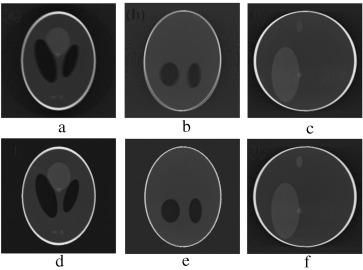

(a–c) Projection at 260°,270° and 280° source position. (d–f) Axial, coronal and ...

Figure 8.

(a–c) Projection at Failed to parse (MathML with SVG or PNG fallback (recommended for modern browsers and accessibility tools): Invalid response ("Math extension cannot connect to Restbase.") from server "https://mathoid.scipedia.com/localhost/v1/":): {\textstyle 260\mbox{°},270\mbox{°}}

and Failed to parse (MathML with SVG or PNG fallback (recommended for modern browsers and accessibility tools): Invalid response ("Math extension cannot connect to Restbase.") from server "https://mathoid.scipedia.com/localhost/v1/":): {\textstyle 280\mbox{°}}

source position. (d–f) Axial, coronal and sagittal slices of the rotational motion corrupted reconstructed volume.